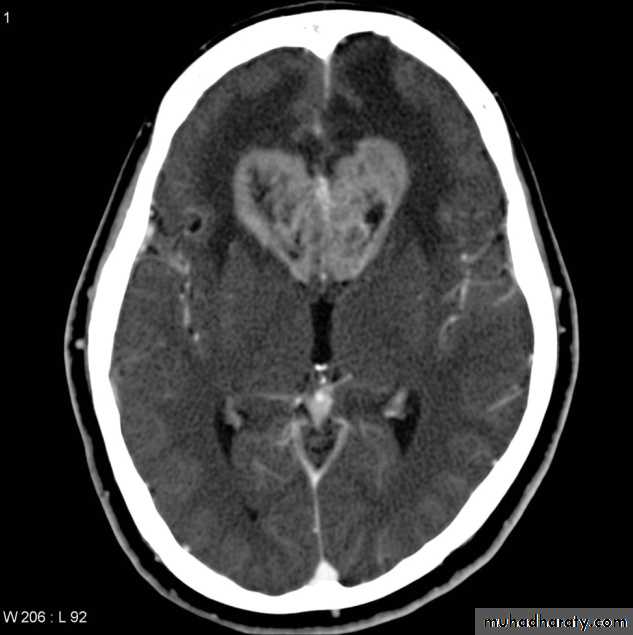

Hydrocephalous

2 types

Obstructive ( non – communicating )

Non –obstructive ( communicating )

No obstruction of the ventricular pathway , but the absorption of the csf at the level of arachnoids' granulation is occluded secondary to lodge by blood clot or inflammatory cell or infection post meningitis most commonly to occur post SAH .

CT Scane